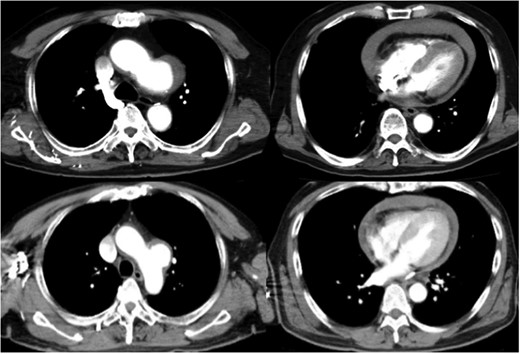

The foramen lacerum at the aneurysm that penetrates the pericardium (arrow).

A 58-year-old man came to the emergency department in our hospital because of the sudden onset of severe back pain. He was alert, his blood pressure was 93/70 mmHg and his heart rate was 102 bpm. Transthoracic echocardiography revealed pericardial effusion. Pericardiocentesis was performed, and it showed bloody fluid. Contrast-enhanced computed tomography showed a distal aortic arch aneurysm and pericardial effusion (Fig. 1), so the diagnosis was intrapericardial rupture of an aortic arch aneurysm, and emergent surgery was performed. At the operation, the heart was covered with coagulation, and we found the foramen lacerum at the aneurysm that penetrated the precardium (Fig. 2). We performed total arch replacement using the same method as described in the first case. The CPB time, aortic clamp time and total circulatory arrest times were 177, 83 and 56 minutes, respectively. The patient recovered well and discharged from the hospital without complication. He was alive and had no complications at 26 months, the time of his last appointment.